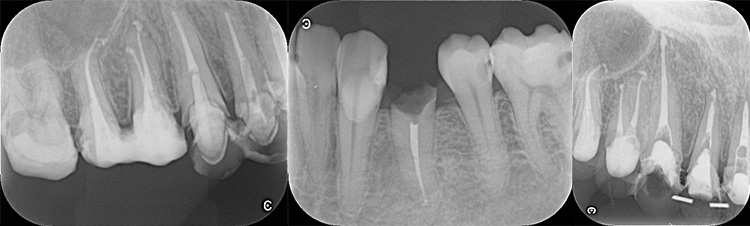

治療前の写真です。歯の根元の黒い部分は膿のたまった袋です。

治療後の写真です。きちんと歯の根の治療(根管治療)を施すことで膿の袋も消失します。